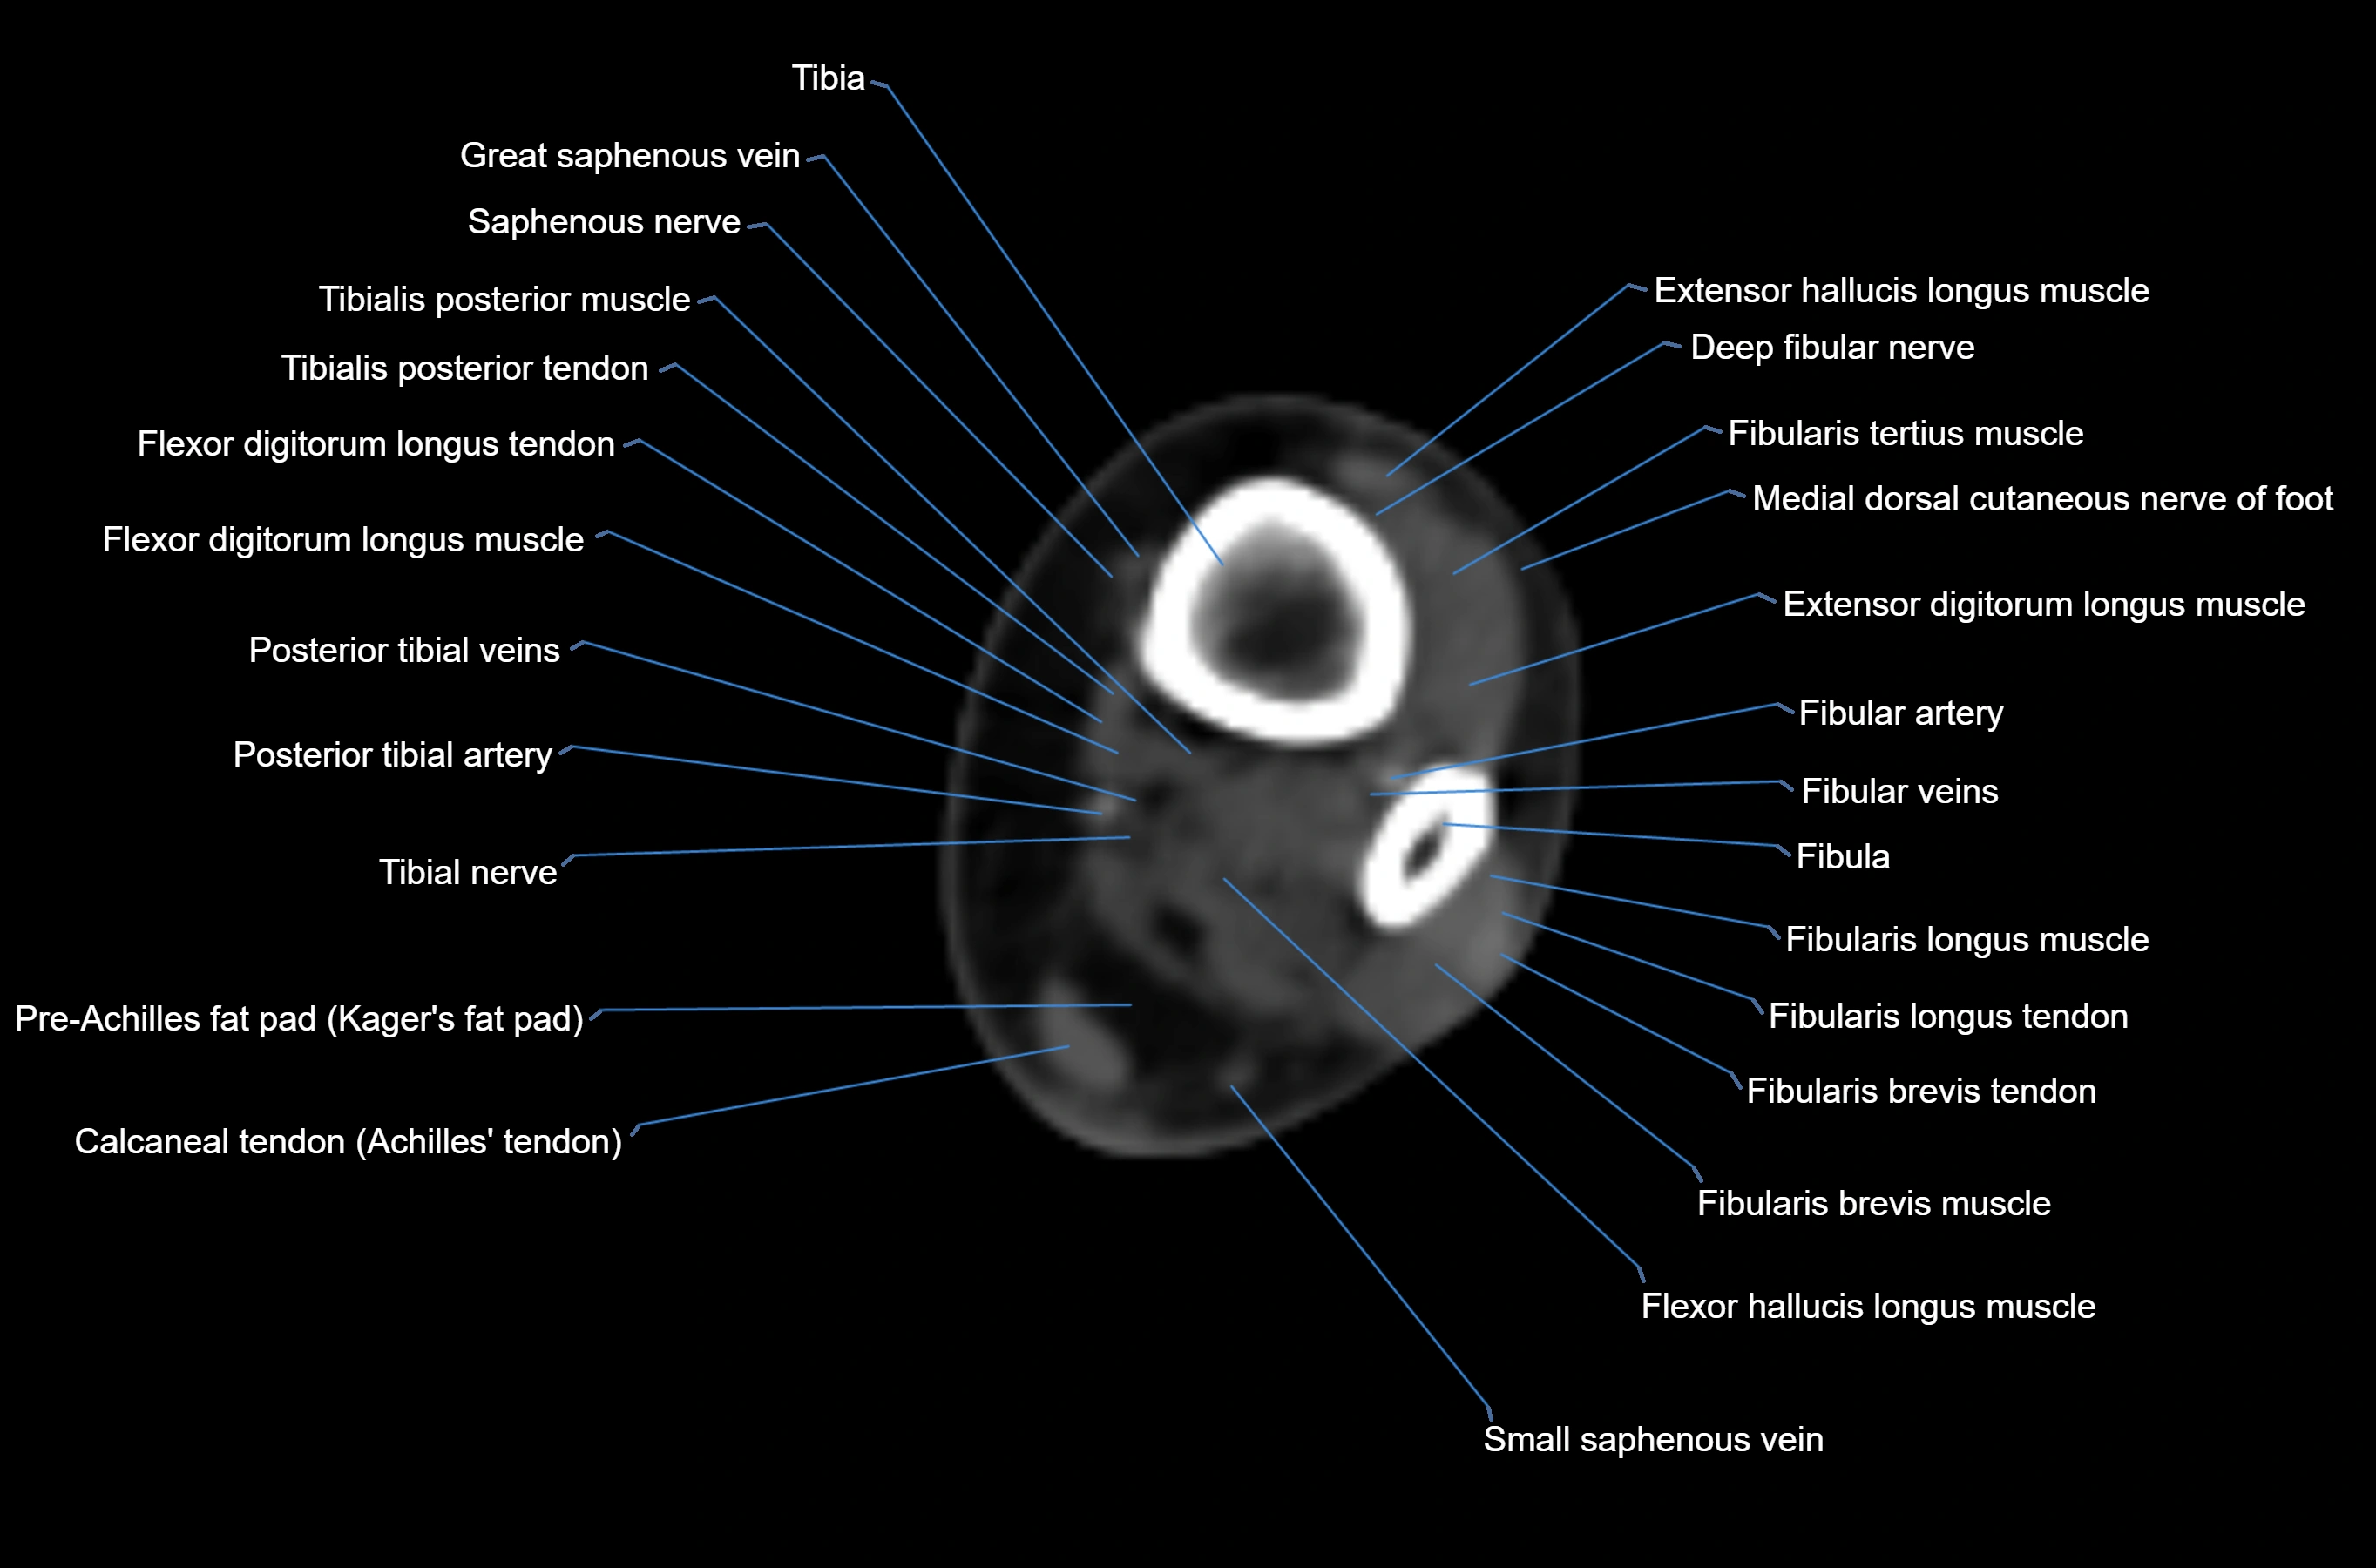

MRI image

CT image